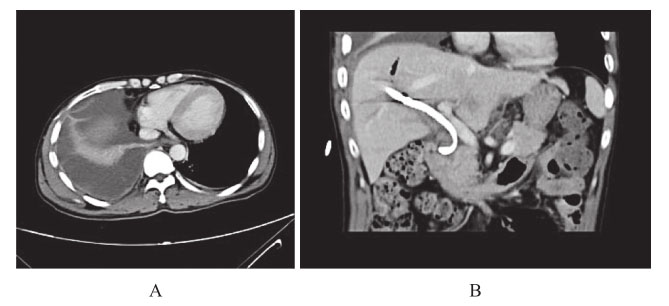

1)胸腹部增强CT:双侧胸腔积液伴两肺膨胀不全,右侧为著。经皮胆道镜碎石取石术后改变,胆管外引流管在位(图5)。

图5 腹部CT:胆管外引流管在位;胸部CT:右侧大量胸腔积液伴右肺不张

2)T管造影:肝内外胆管未见明显充盈缺损,胆总管下段通畅(图6)。

图6 T管造影

3)胸部超声提示:右侧大量胸腔积液,包裹性积液伴分隔。